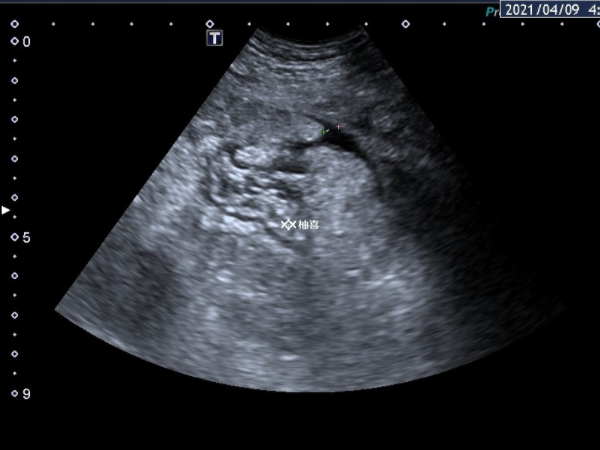

中度腹水常常需要到医院进行进一步的检查,如超声检查来评估腹水的量和卵巢的情况。医生会根据检查结果给予相应的药物治疗,一般会使用白蛋白。白蛋白可以提高血浆胶体渗透压,使渗出到腹腔的液体重新回到血管内,从而减轻腹水。同时,也可能会使用一些利尿药物,如呋塞米。